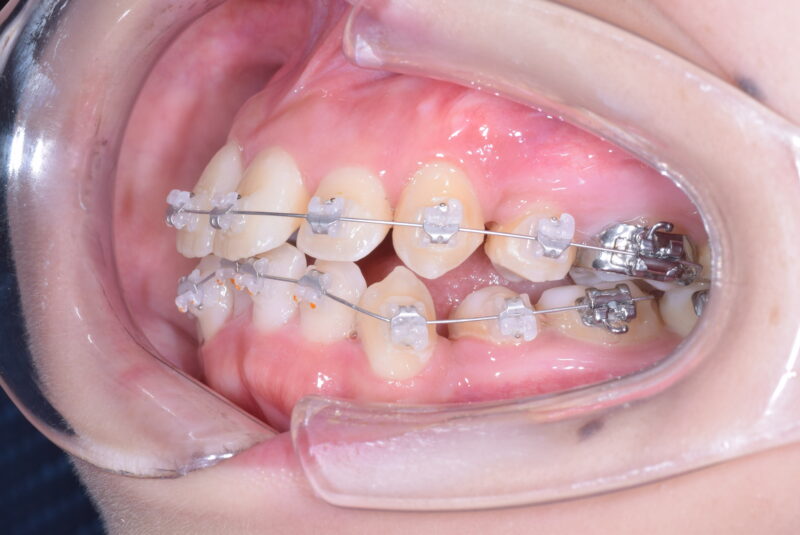

症例27 重度叢生症例

・治療前

・治療中

・治療後

①主訴 歯ならびが悪い

②診断名 前歯部叢生 Angle Cl. I

③年齢 20代女性

④治療に用いた主な装置 上顎:表側の装置 下顎:表側の装置

⑤抜歯部位 上顎:左右第一小臼歯 下顎:左右第一小臼歯

⑥治療期間 1年5か月

⑦治療費 850,000円

⑧リスク副作用 痛み・治療後の後戻り・歯根吸収・歯髄壊死・歯肉退縮などが一般的なリスクと副作用です。